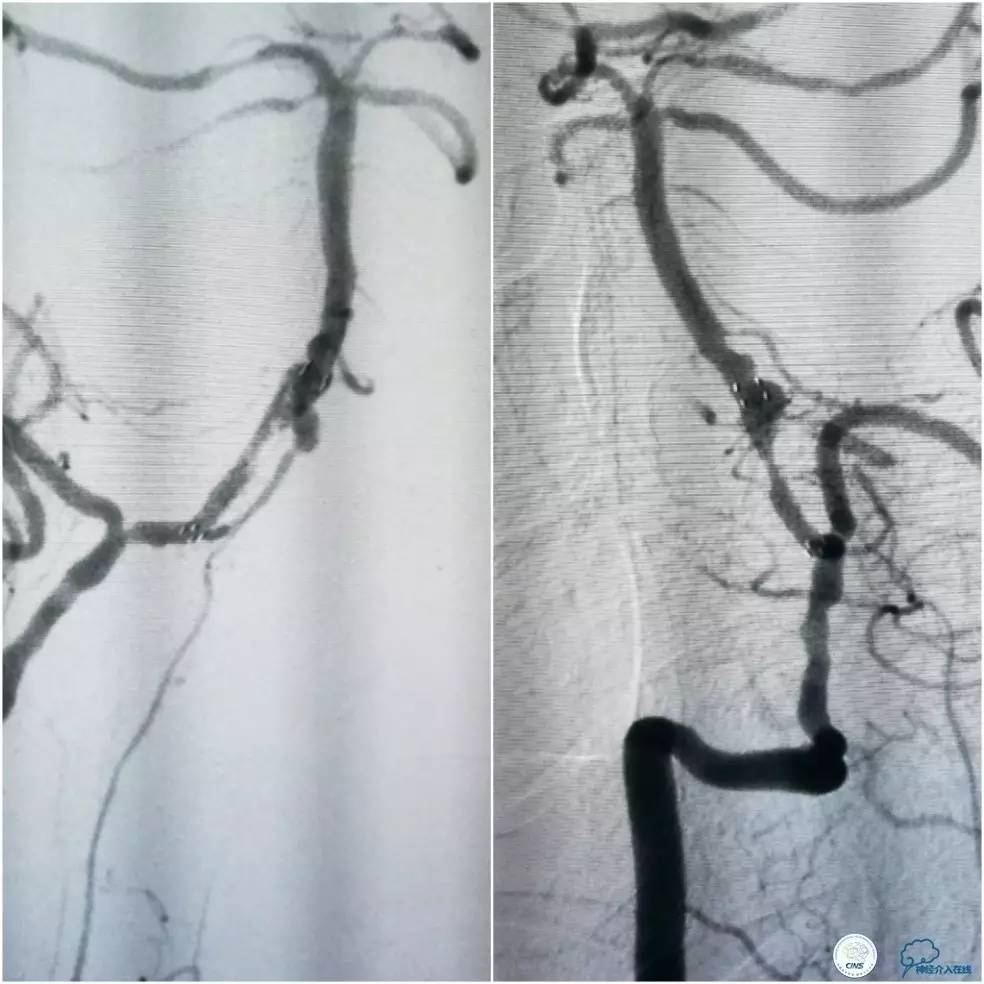

术前DSA:右椎动脉V1段长段重度狭窄,V4-基底动脉交界区显影浅淡,狭窄程度重,但具体程度显示欠佳(图7)。左椎动脉V1段闭塞,左椎动脉V2远段经侧支代偿显影,V3段以远未见显影(图8)。前循环造影未见明显前循环向后循环代偿(图9)。

图7

图8

图9

1. 患者右椎动脉优势,右椎动脉V1段长段重度狭窄、V4段-基底动脉重度狭窄(或者闭塞)。左椎动脉V1段闭塞,经侧支代偿的左椎动脉V3段以远未见显影亦考虑闭塞,拟处理右椎动脉。

2. 右椎动脉V1段狭窄程度重,病变长度长,但病变血管较为平直,估计先处理近端病变后导引导管越过支架难度不大,故决定先处理近端病变再处理远端病变。

3. 右椎动脉V4段-基底动脉长段狭窄,CT提示局部钙化明显,预计发生术中扩张困难的机率高,拟采用球囊预扩张,再放置自膨支架。